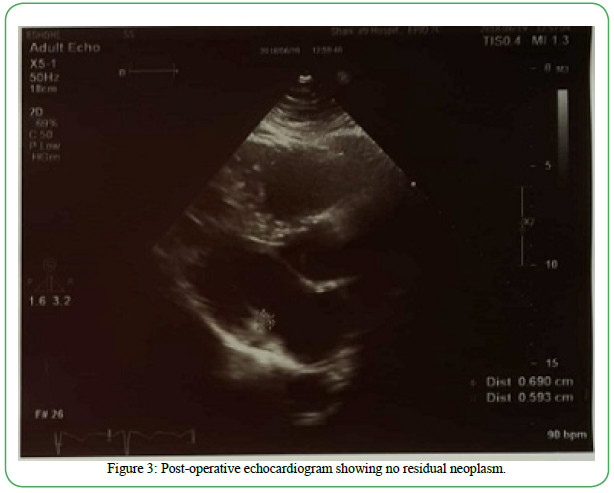

A 35-year-old Iranian otherwise healthy man was referred to the hospital with a one month history of palpitation, dyspnea on exertion, and chest discomfort. His vital signs and physical exam were unremarkable. Echocardiogram showed a heterogenous round shape mobile mass measuring 41mm x 28 mm, in the LA originating from the anterior mitral valve and protruding through the mitral valve in diastole (suggestive of either atrial myxoma or papillary fibroelastoma) (Figure 1). Computed Topography Angiography (CTA) of coronary arteries (CA) showed CA-score of 0 and a filling defect in the LA with a 35 mm protrusion to the mitral valve and attachment to the lateral left atrial wall, which also suggested atrial myxoma. A diagnosis of left atrial mass with mild mitral regurgitation and mild tricuspid insufficiency was made. Flow velocity measurements (FVM) showed that the atrial mass was producing obstruction to the flow at the mitral level (Peak Gradient = 22.11 mmHg) (Figure 2). Due to the outflow obstructive nature of the tumor, urgent cardiac surgical intervention was indicated.

Figure 2. Flow velocity measurement showing the tumor was producing obstruction to the flow at the mitral level (Peak Gradient = 22.11 mmHg)